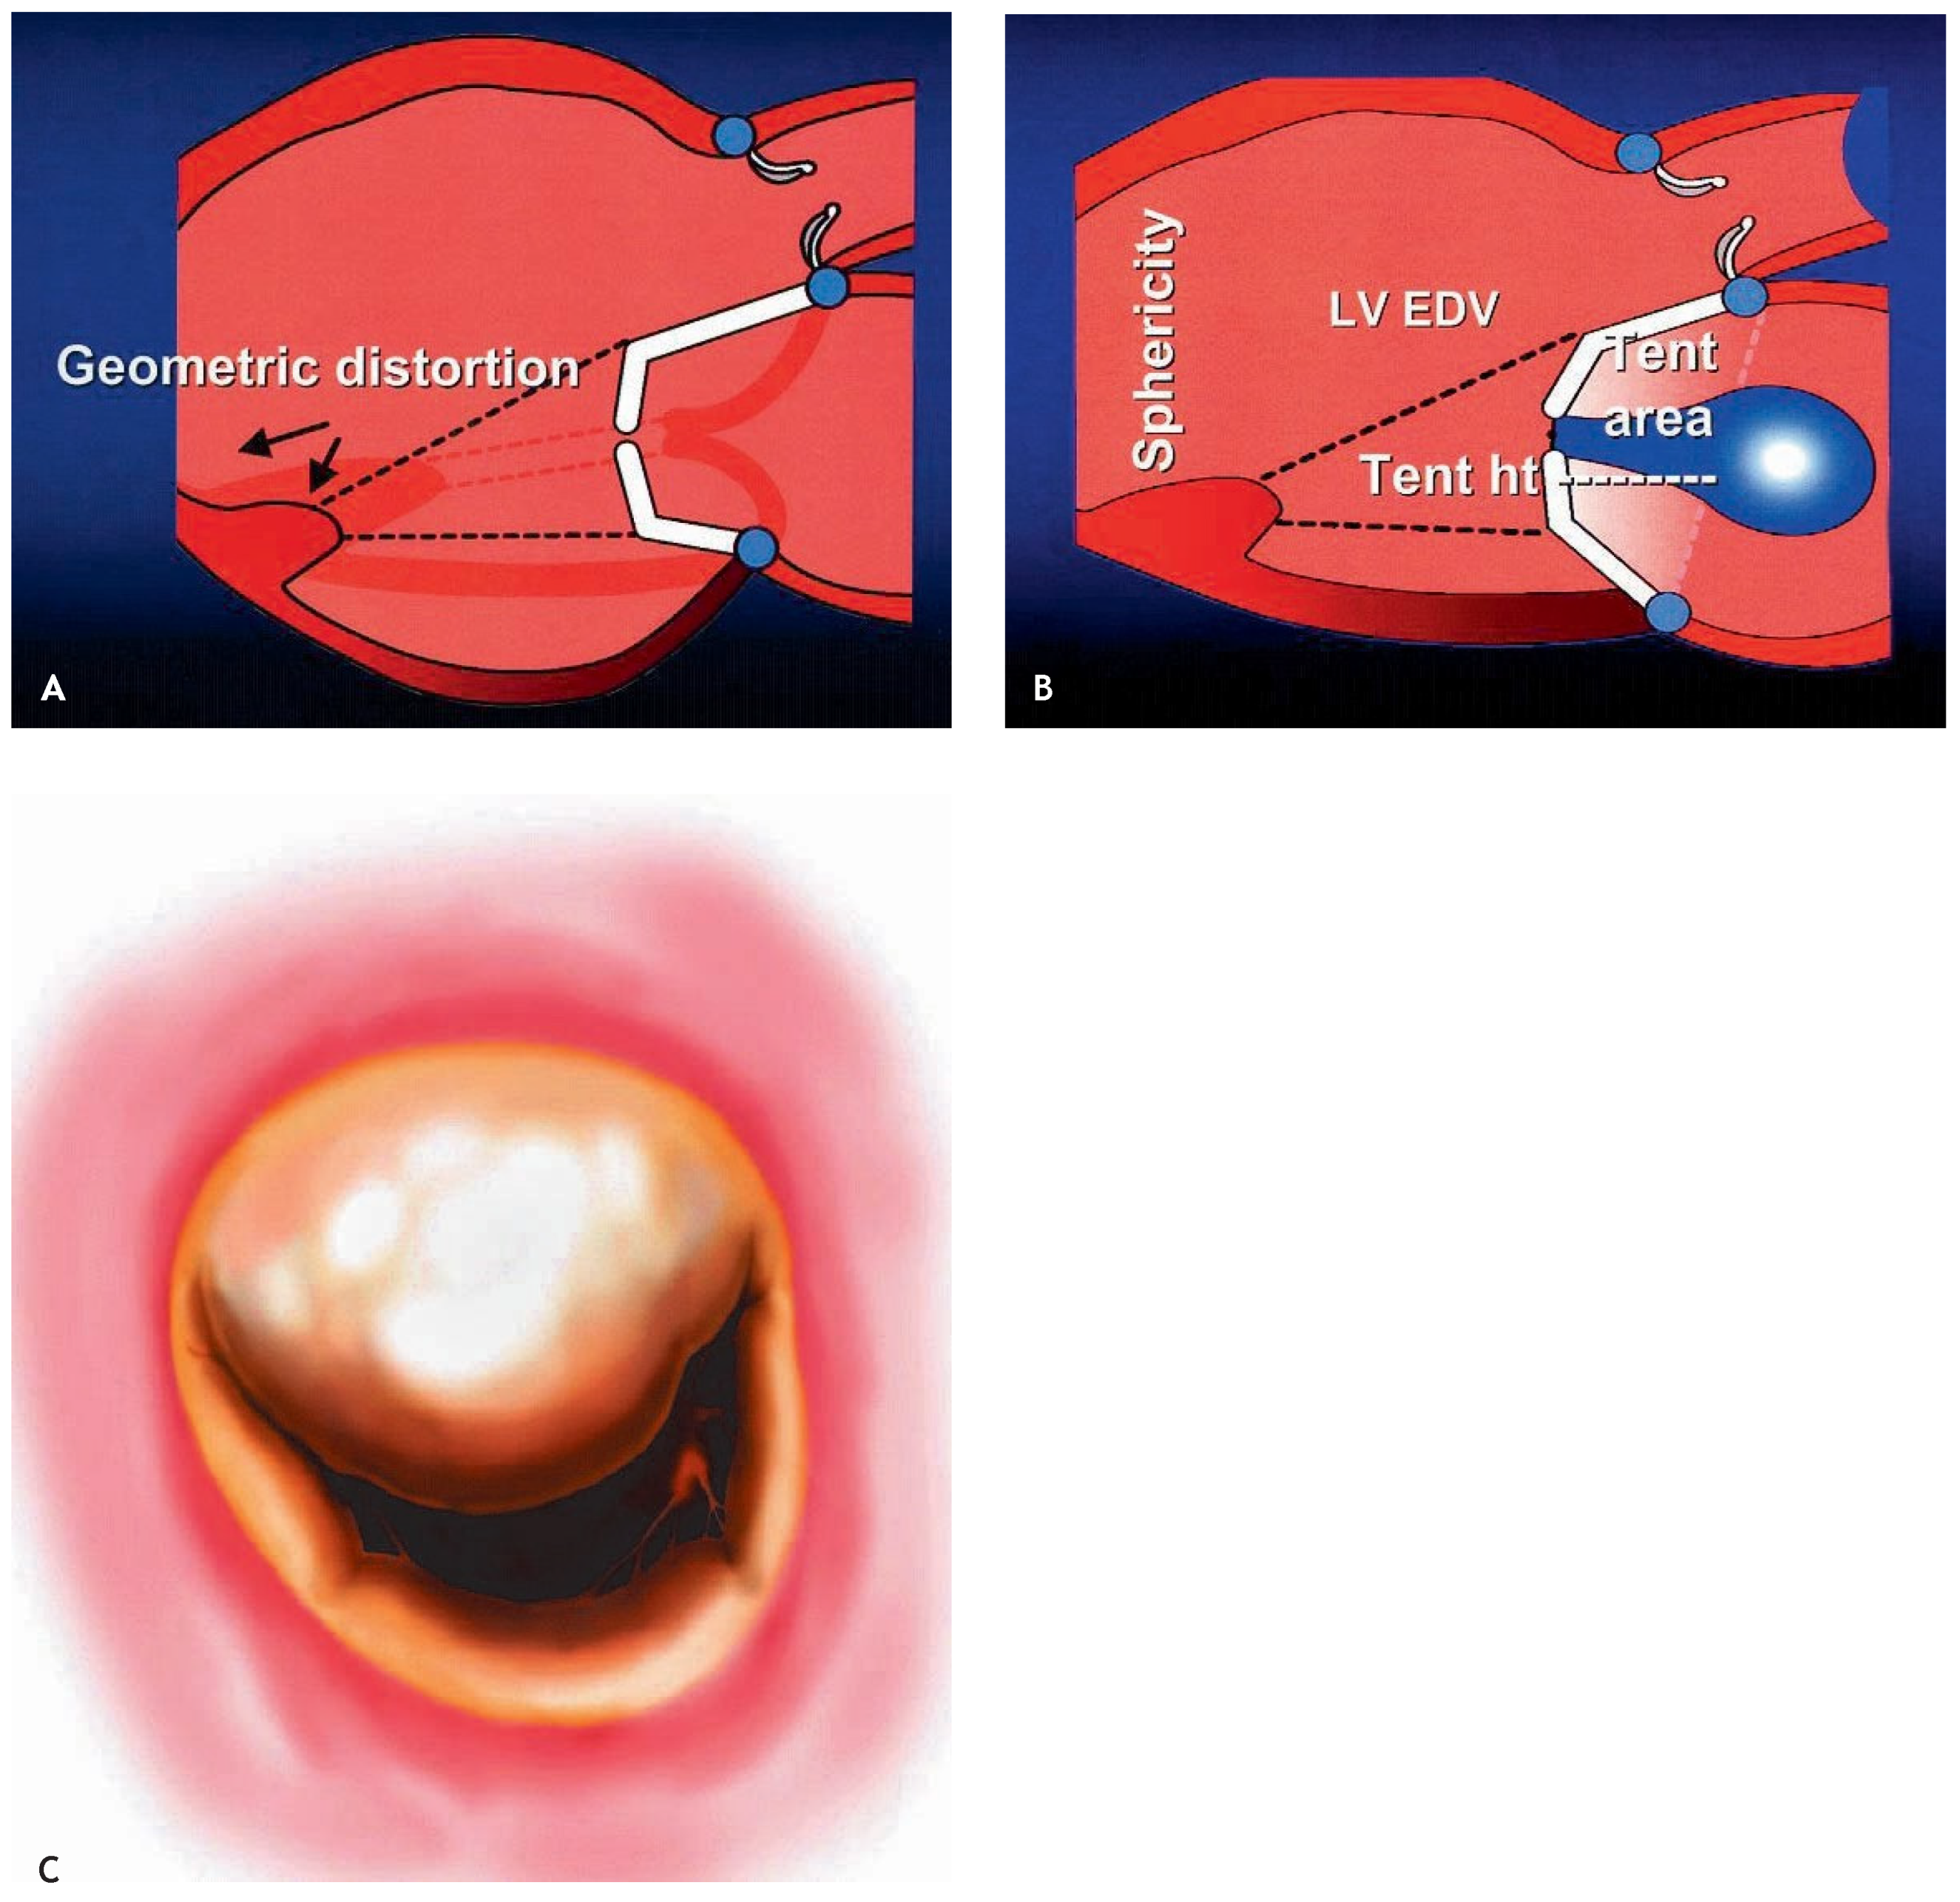

Ischaemic mitral regurgitation (IMR) is defined as functional MR in the presence of a morphologically normal mitral valve. Common features of IMR are systolic restriction of leaflet motion (the so-called tethering effect), apical and lateral displacement of the subvalvular apparatus, annular dilatation and normal valve morphology (Figure 1A). Typically, patients with IMR present with LV dilatation and impaired systolic function in the setting of ischaemic or idiopathic dilated cardiomyopathy (CMP). Left ventricular dilatation leads to dilatation of the mitral annulus and to apical and lateral displacement of one or both papillary muscles with tethering of the valve leaflets and consecutive IMR. IMR is therefore thought to be primarily a ventricular and not a valvular problem. With idiopathic dilated CMP, dilatation is usually symmetrical, resulting in symmetrical mitral distortion and a central jet (Figure 1A,B). With ischaemic CMP an asymmetrical jet with tethering of the P3 segment of the mitral valve due to inferior infarction is frequently present (Figure 1C). However, a central jet may also be seen years after myocardial infarction with global ventricular dilatation due to remodeling. While acute IMR is thought to be frequent in the setting of AMI and may resolve spontaneously in milder forms [1], the prevalence of chronic IMR persisting after 6 weeks [2] is largely unknown. Its presence however, is known to significantly impair patient survival and increase the risk of congestive heart failure [1,3,4]. Clinically, patients may be asymptomatic with respect to IMR, presenting perhaps signs of myocardial ischaemia in coronary artery disease, but may also be symptomatic with dyspnea or signs of congestive heart failure in the most severe cases with impaired LV function, severe IMR and severely dilated LV.

Figure 1.

(A) Ischaemic MR caused by geometric distortion of the valve following LV dilatation with apical and lateral displacement of the papillary muscle apparatus. (B) Ventricular displacement of the leaflets creates an area called tenting area with the tenting height (tent ht), an index of severity of valvular tethering. (LV EDV = LV enddiastolic volume). (C) Surgical view of the mitral valve from the left atrium demonstrating typical tethering of P3 in ischaemic cardiomyopathy following inferior myocardial infarction, resulting in IMR with an asymmetrical jet.